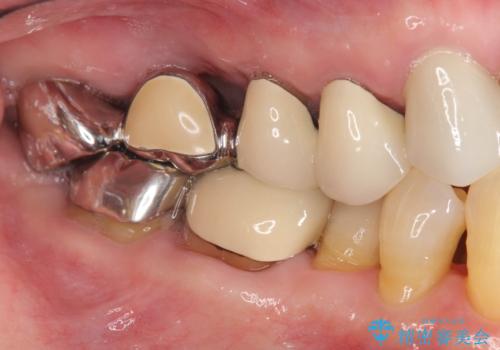

- 数年前にいれた右上のブリッジが、「ぐらついて痛い、噛めない。」と改善を希望され来院されました。

X線写真より、咬合力負担能力に十分で無い親知らずを使用した長いブリッジが装着されており、力の負担に耐え切れずぐらつきが増加してきた状態です。

親知らず、ブリッジを抜去・撤去しインプラントを用いた咬合機能回復を行っていくこととしました。